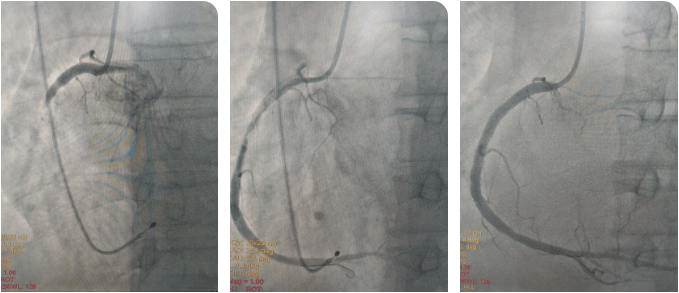

時(shí)間就是生命!心內(nèi)科介入團(tuán)隊(duì)與死神展開較量,大家輪流為患者進(jìn)行心肺復(fù)蘇,并以最快的速度完成消毒、鋪巾。患者大動(dòng)脈搏動(dòng)消失,李新國主任、吳利杰主任憑借扎實(shí)的基本功,盲穿腋靜脈及右側(cè)股動(dòng)脈,植入臨時(shí)起搏器。根據(jù)心電圖判斷罪犯血管為右冠狀動(dòng)脈,李新國主任果斷直接選擇右冠指引導(dǎo)管造影,造影證實(shí)判斷,右冠狀動(dòng)脈粗大,自近段完全閉塞。12:36介入團(tuán)隊(duì)將導(dǎo)絲送到了患者閉塞血管的遠(yuǎn)端,并用球囊對閉塞血管擴(kuò)張后順利恢復(fù)前向血流。奇跡出現(xiàn)了,患者微弱的心跳逐漸有力,血壓、心律也逐漸好轉(zhuǎn)。此時(shí)的患者仍處于昏迷狀態(tài),攜帶呼吸機(jī)及臨時(shí)起搏器轉(zhuǎn)入CCU病房繼續(xù)治療。

術(shù)后,在李新國主任、沈靖超主治醫(yī)師及段秋燕護(hù)士長帶領(lǐng)的護(hù)理團(tuán)隊(duì)精心施治、細(xì)心護(hù)理下,患者于當(dāng)日意識轉(zhuǎn)清醒,拔除氣管插管,生命體征穩(wěn)定,之后也順利渡過心梗后心力衰竭、消化道應(yīng)激性潰瘍、肺部感染等并發(fā)癥,3天后拔除臨時(shí)起搏器,1周后于右冠狀動(dòng)脈動(dòng)脈植入2枚支架,之后轉(zhuǎn)入普通病區(qū)繼續(xù)鞏固治療,并于近期順利出院。